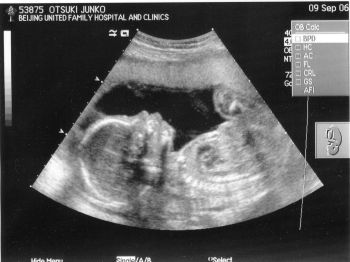

| 2006-08-23 北京渡航前に | 2006-09-09 北京にて(横顔くっきり!) | |